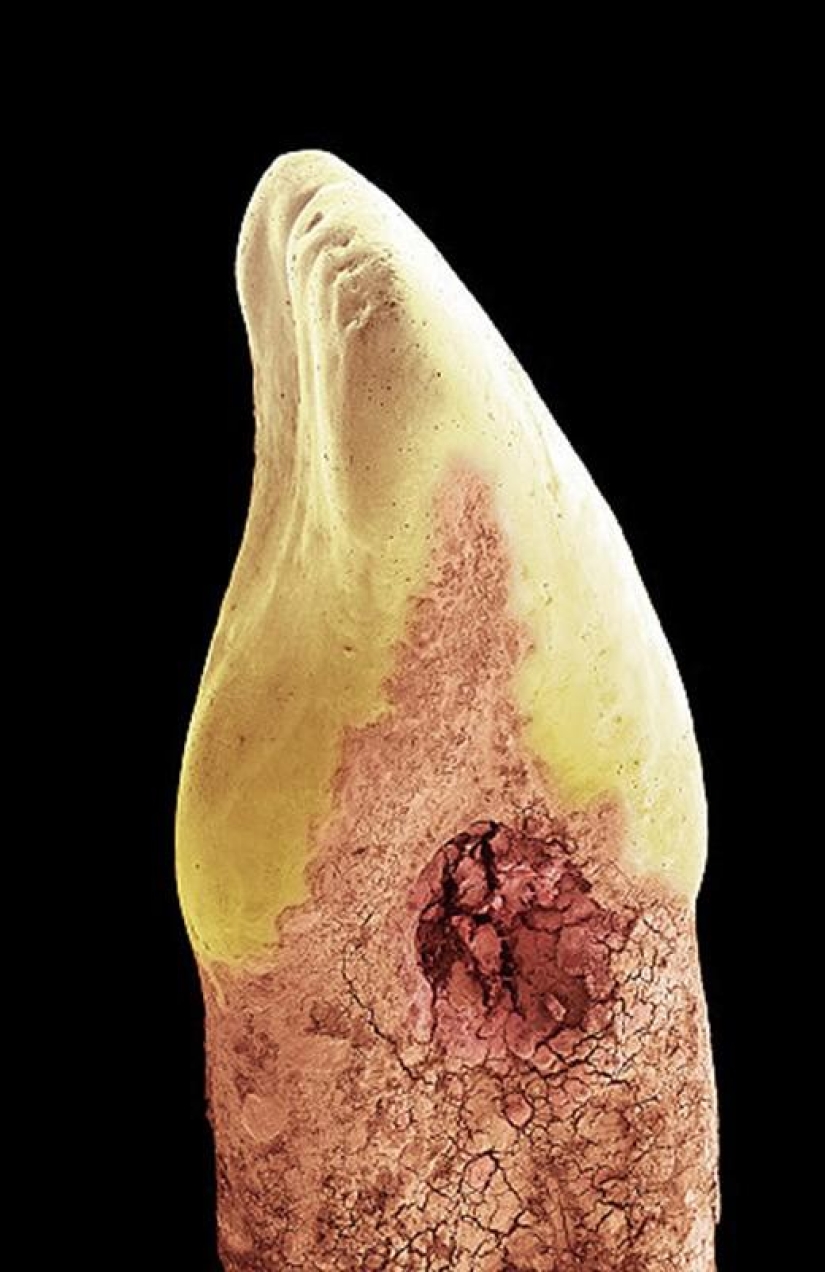

Baby tooth. Most human teeth are made of dentin, a substance that lines the cavity that contains soft connective tissue, blood vessels, and nerves. The crown of the tooth is then covered by enamel (white in the photo above), a stronger and more mineralized substance that protects dentin from acids in the mouth. At the root of a tooth, dentin is protected by a substance called cementum (pink), which serves as a means by which the periodontal ligaments can attach to the tooth for stability. (SPL/Barcroft Media)

Crown of a baby tooth. Its root has become separated through a process known as temporary tooth resorption. This was caused by pressure from the growing permanent tooth. (SPL/Barcroft Media)